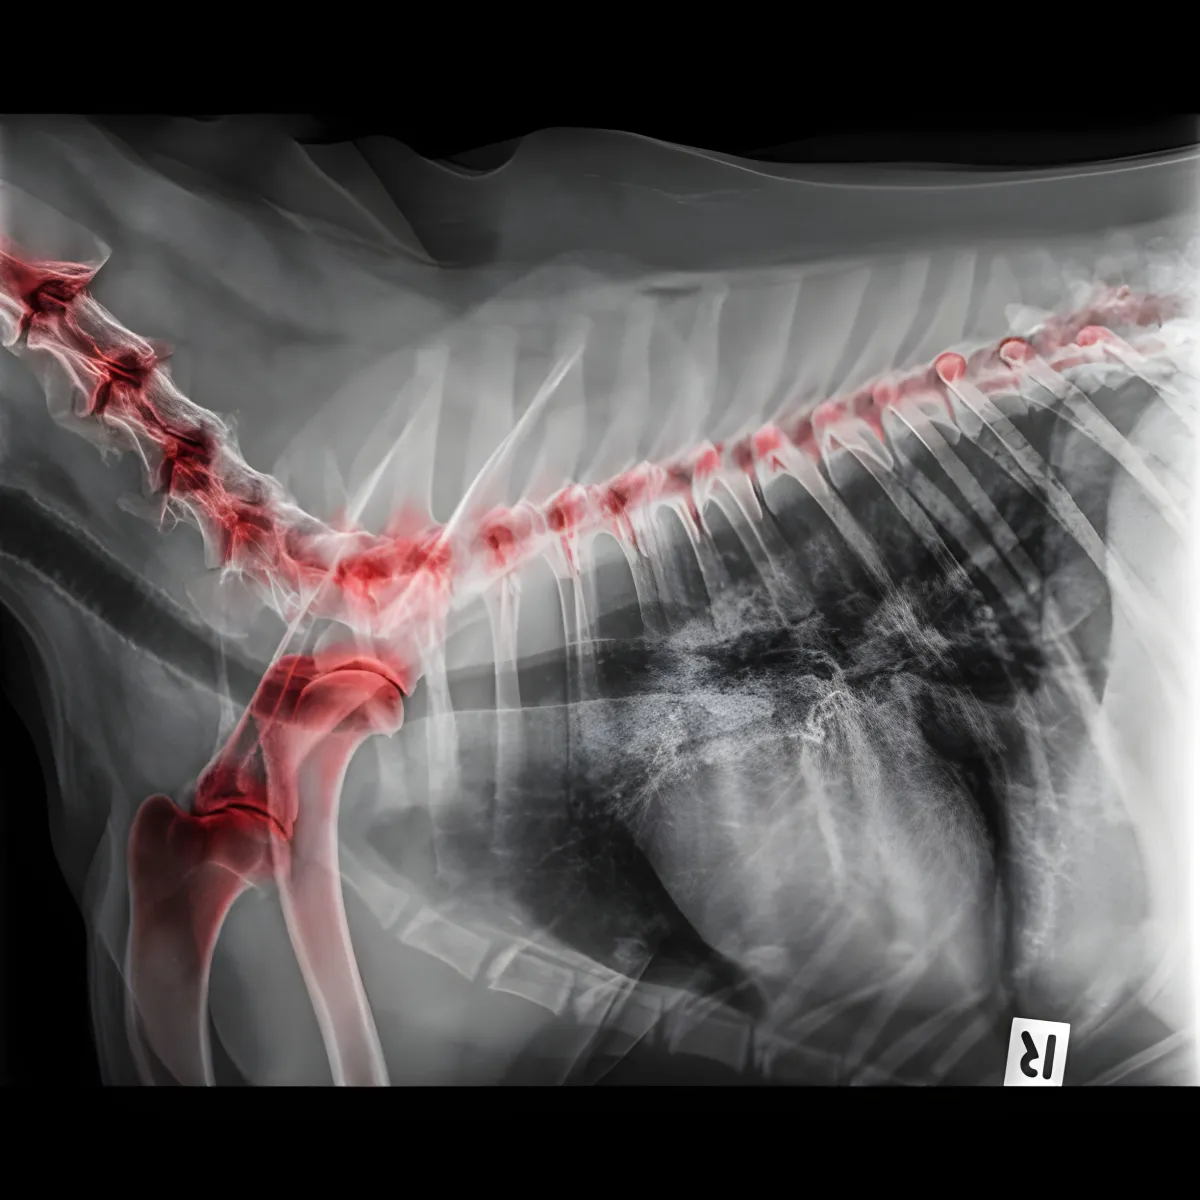

CBD Memperbaiki Keadaan Artritis pada Pinggul, Lutut, dan Belakang Anjing

CBD Memperbaiki Keadaan Artritis pada Pinggul, Lutut, dan Belakang Anjing CBD boleh membantu mengurangkan masalah artritis pada anjing. Jadi, berapakah dos CBD yang sepatutnya anda berikan kepada mereka?

Namun, keadaan ini mungkin akan berubah tidak lama lagi berkat penemuan terkini oleh sekumpulan penyelidik di Baylor College of Medicine di Houston, Texas. Mereka telah menjalankan satu kajian untuk menilai kesan terapeutik CBD dalam merawat kesakitan artritis pada anjing. Para penyelidik ini berharap bahawa penemuan mereka dapat memberikan pencerahan tentang bagaimana CBD mungkin dapat membantu manusia yang mengalami keadaan yang sama.

Kajian ini telah diterbitkan dalam jurnal perubatan PAIN. Dalam kajian ini, didapati bahawa CBD mampu mengurangkan penghasilan molekul inflamasi dan sel imun yang berkaitan dengan arthritis secara ketara, baik dalam ujian makmal mahupun model tikus. Sementara itu, dalam kajian yang memfokuskan kepada anjing, rawatan CBD menunjukkan peningkatan yang ketara dalam kualiti hidup anjing-anjing tersebut, seperti yang dinilai oleh pemilik dan doktor haiwan.

Berikutan hasil yang memberangsangkan dalam model tikus, para penyelidik beralih kepada menilai kesan CBD pada anjing yang mengalami arthritis. Halpert menjelaskan keputusan ini dengan berkata, "Kami memilih untuk mengkaji anjing kerana bukti eksperimen menunjukkan bahawa model arthritis yang berlaku secara spontan, terutamanya dalam anjing peliharaan, lebih sesuai untuk menilai rawatan kesakitan arthritis manusia berbanding model haiwan lain. Ciri-ciri biologi arthritis pada anjing sangat mirip dengan keadaan manusia."